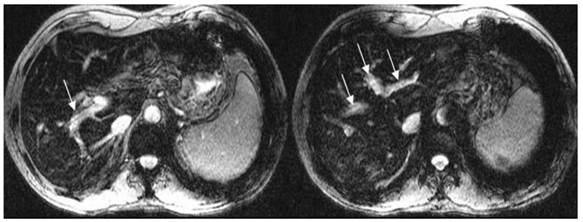

Direct Portal Vein Thrombosis Visualization With T2 Weighted Magnetic Resonance Imaging